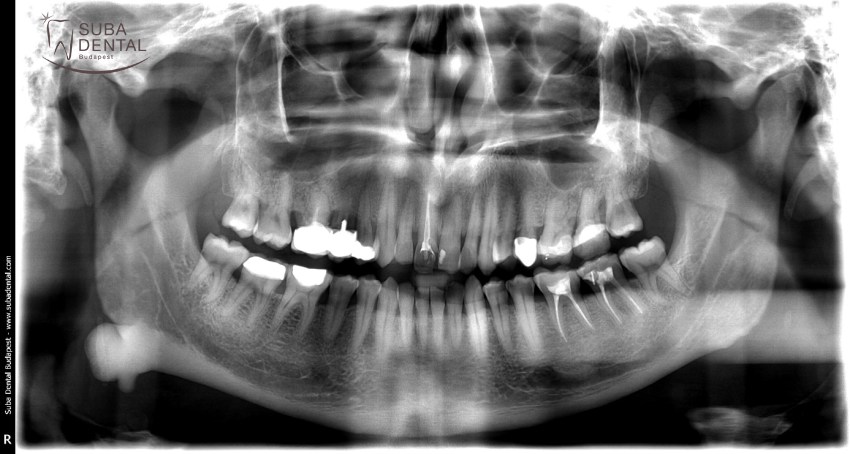

Panoramic radiograph of chronic dental foci, teeth affected by periodontal disease, and root remains. All teeth had to be extracted

Follow-up panoramic radiograph following the installation of implants. Our patient would have needed a bone graft but was completely inconvincible. Therefore, a total of 4 implants were installed per jawbone that would support a bar denture. The dental foci and infections totally destroyed bone width and bone height as a result of which the mounting of implants required great effort and could only be carried out in an asymmetric fashion.

Panoramic radiograph of the lower and upper bar